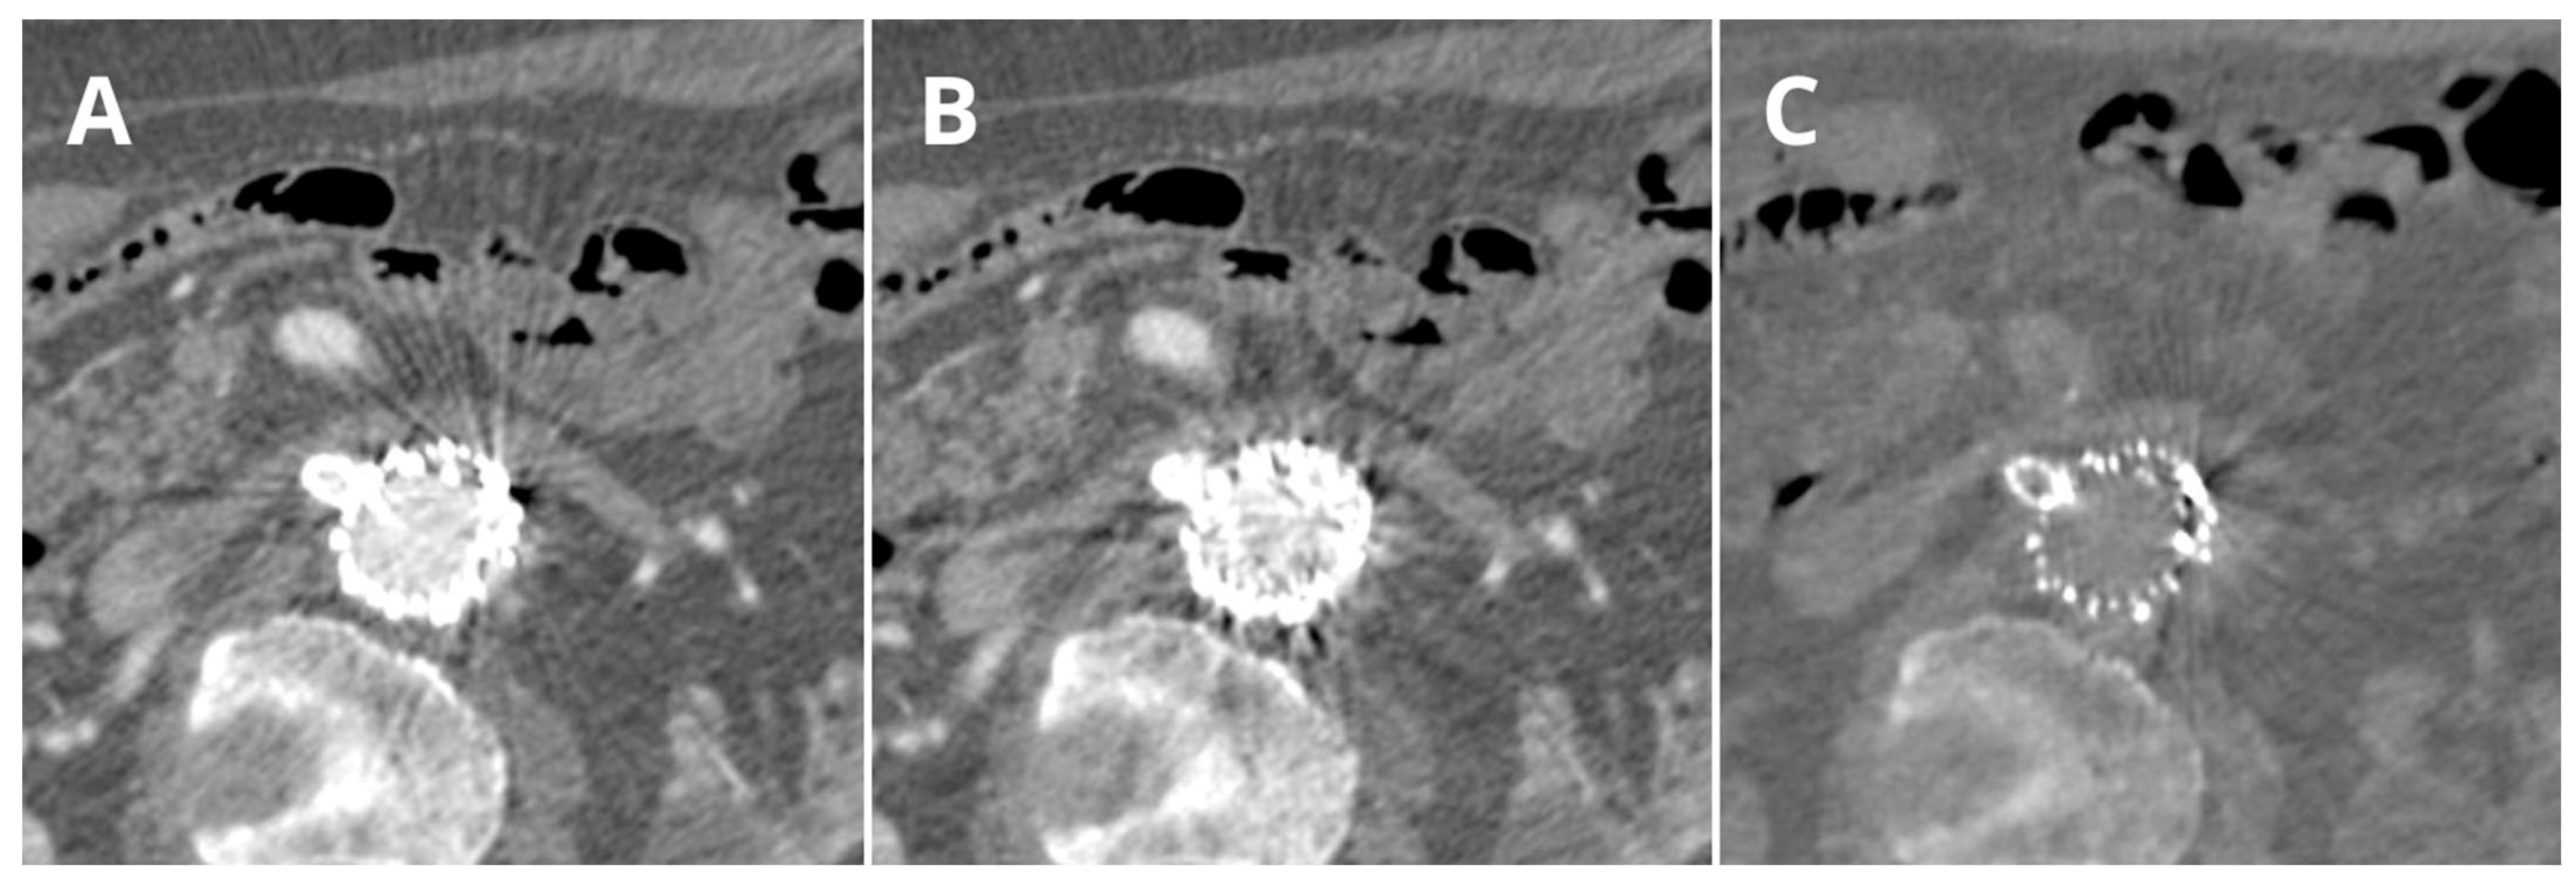

- Boos, J.; Fang, J.; Heidinger, B.H.; Raptopoulos, V.; Brook, O.R. Dual energy CT angiography: Pros and cons of dual-energy metal artifact reduction algorithm in patients after endovascular aortic repair. Abdom. Radiol. 2017, 42, 749–758. [Google Scholar] [CrossRef]

- Ragusi, M.A.A.D.; van der Meer, R.W.; Joemai, R.M.S.; van Schaik, J.; van Rijswijk, C.S.P. Evaluation of CT Angiography Image Quality Acquired with Single-Energy Metal Artifact Reduction (SEMAR) Algorithm in Patients after Complex Endovascular Aortic Repair. Cardiovasc. Interv. Radiol 2018, 41, 323–329. [Google Scholar] [CrossRef] [PubMed]

- Kazimierczak, W.; Nowak, E.; Kazimierczak, N.; Jankowski, T.; Jankowska, A.; Serafin, Z. The value of metal artifact reduction and iterative algorithms in dual energy CT angiography in patients after complex endovascular aortic aneurysm repair. Heliyon 2023, 9, e20700. [Google Scholar] [CrossRef]